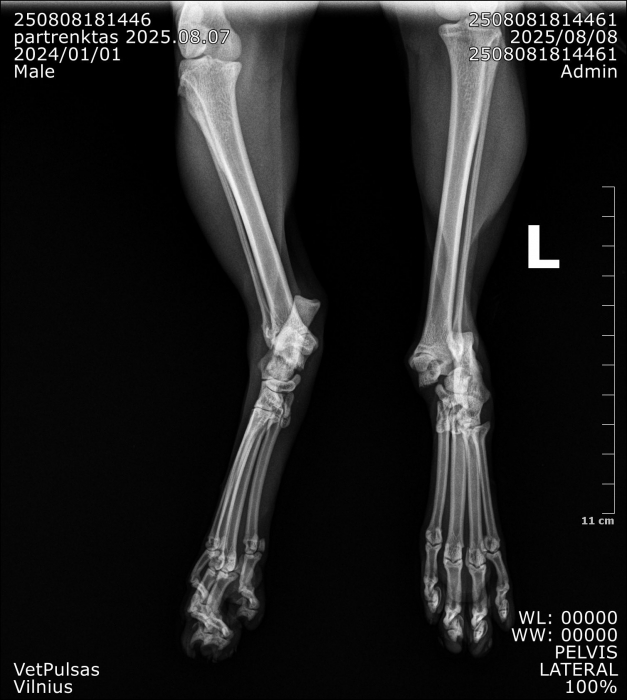

Į veterinarijos kliniką žmonės atvežė automobilio nutrenktą katinuką. Atlikus rentgeną paaiškėjo, kad abi užpakalinės kojos per sąnarius suknežintos į skeveldras. Vienos kojos raiščiai nutraukti. Apžiūrėjusi nuotraukas ir įvertinusi skeveldrinius lūžius chirurgė informavo kad operacija bus itin sudėtinga ir brangi. Vienu metu ji galėtų atlikti tik vienos kojytės operaciją, o po savaitės ar daugiau žiūrint kokia gyvūno būklė galės operuoti antrą. Visa tą laiką katinukas bus klinikos stacionare.

Chirurgė perspėjo kad operacija, gydymas ir pooperacine slauga klinikoje kainuos tikrai pakankamai daug nes užtruks mėnesį ar net daugiau laiko.